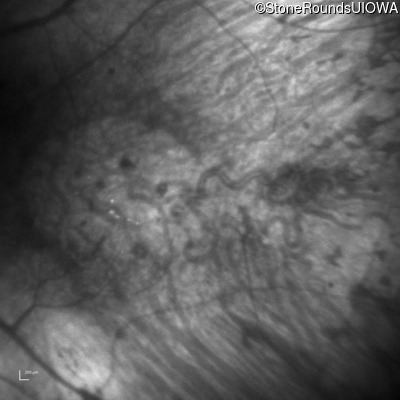

Infrared Fundus Photograph - Right - Hand Motion 1' sc

Exemplar

Infrared Fundus Photograph - Left - Hand Motion 6" sc